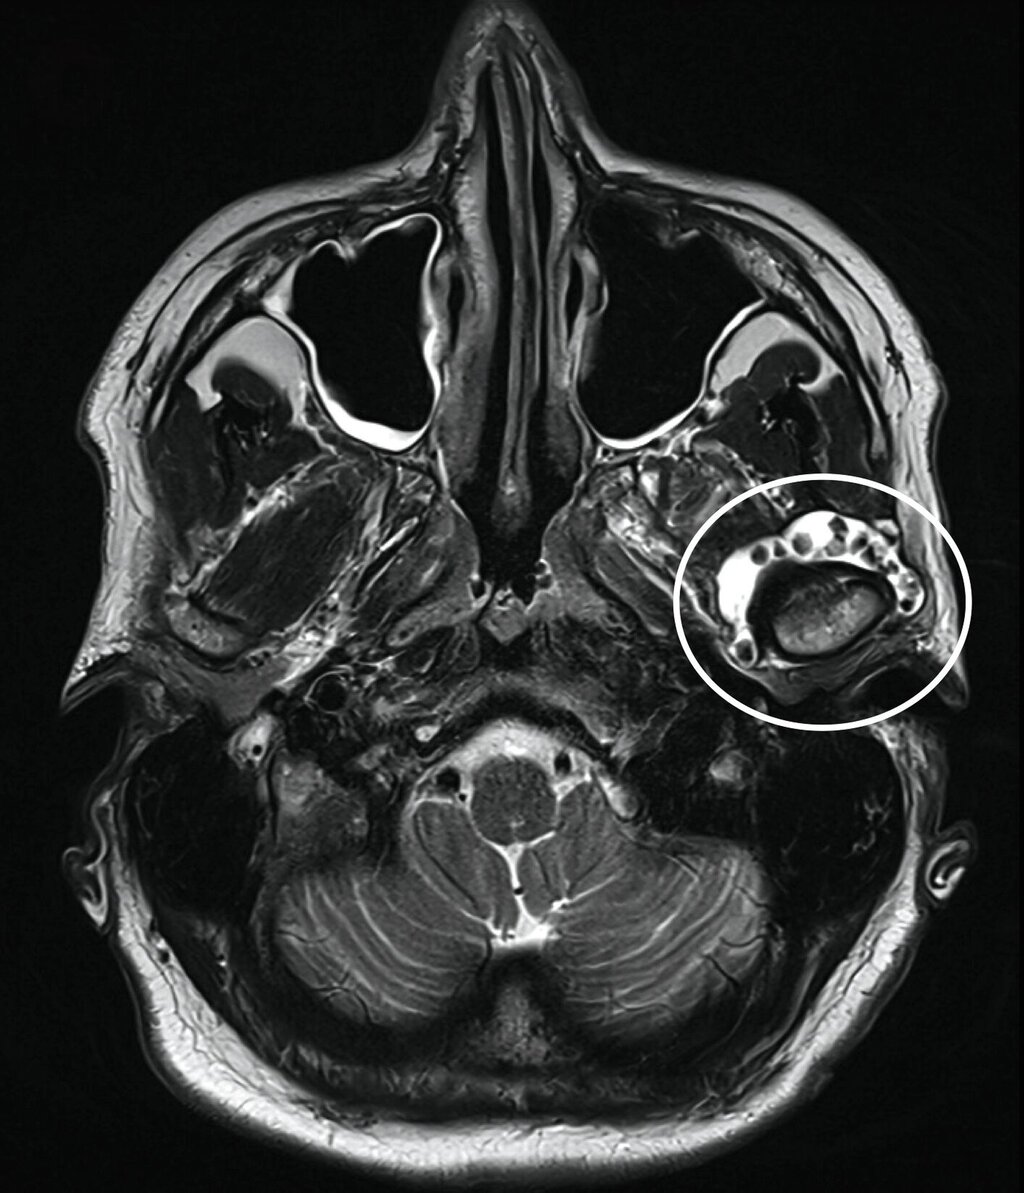

Klinisch zeigte sich kein Hinweis auf eine Myopathie der Kaumuskulatur. Zudem waren weder eine Mundöffnungsbehinderung noch ein Kiefergelenkgeräusch detektierbar. In Anbetracht der klinischen und der radiologischen Verdachtsdiagnose wurde eine Magnetresonanztomografie durchgeführt (Abbildung 2), die eine deutliche Flüssigkeitskollektion zirkulär im Bereich des linken Kiefergelenks mit multiplen, a. e. hyalinen Fragmenten sichtbar macht.

Die differenzialdiagnostische Abklärung erfolgt nach eingehender Anamnese und klinischer Untersuchung zunächst über die bildgebende Darstellung mittels Magnetresonanztomografie, da die nicht verkalkten Gelenkkörper in der Nativ-Computertomografie (und in der Digitalen Volumentomografie) nicht oder nur sehr spät nachweisbar sind. Die Panoramaschichtaufnahme ist gerade in frühen Phasen der Erkrankung häufig nicht zielführend. In späten Erkrankungsstadien können die Distraktion des Gelenkspalts oder die sekundäre Verkalkung auf das Vorhandensein der Gelenkkörper hinweisen [Reich und Neff, 2022].

Die MRT ist die bildgebende Methode der Wahl.